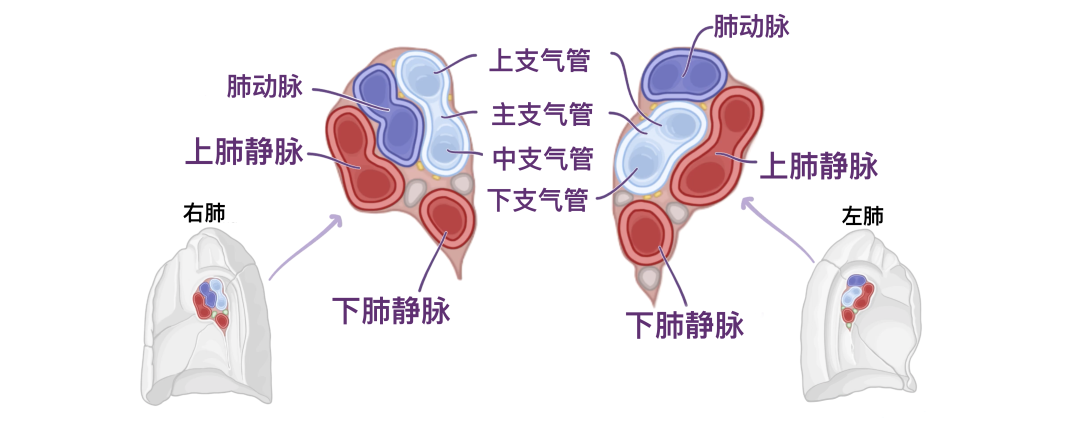

在右肺根和左肺根的切片上,我们可以识别主支气管的位置以及肺动脉和静脉的相互关系。但请记住,人与人之间可能存在细微差异。首先,主支气管通常紧靠两个肺根的后中边界。根据切片的精确位置,您可能会看到主支气管在右侧分为上叶支气管和中叶支气管,在左侧分为上叶支气管和下叶支气管。

在解剖学上,支气管是最容易识别的,因为触摸时其软骨结构坚固。其次,肺动脉是左根和右根上最高级的结构。然而,在右侧,您可能会看到肺动脉的前两个分支。第三,上肺静脉和下肺静脉通常是两个肺根上最前面和最下面的结构。